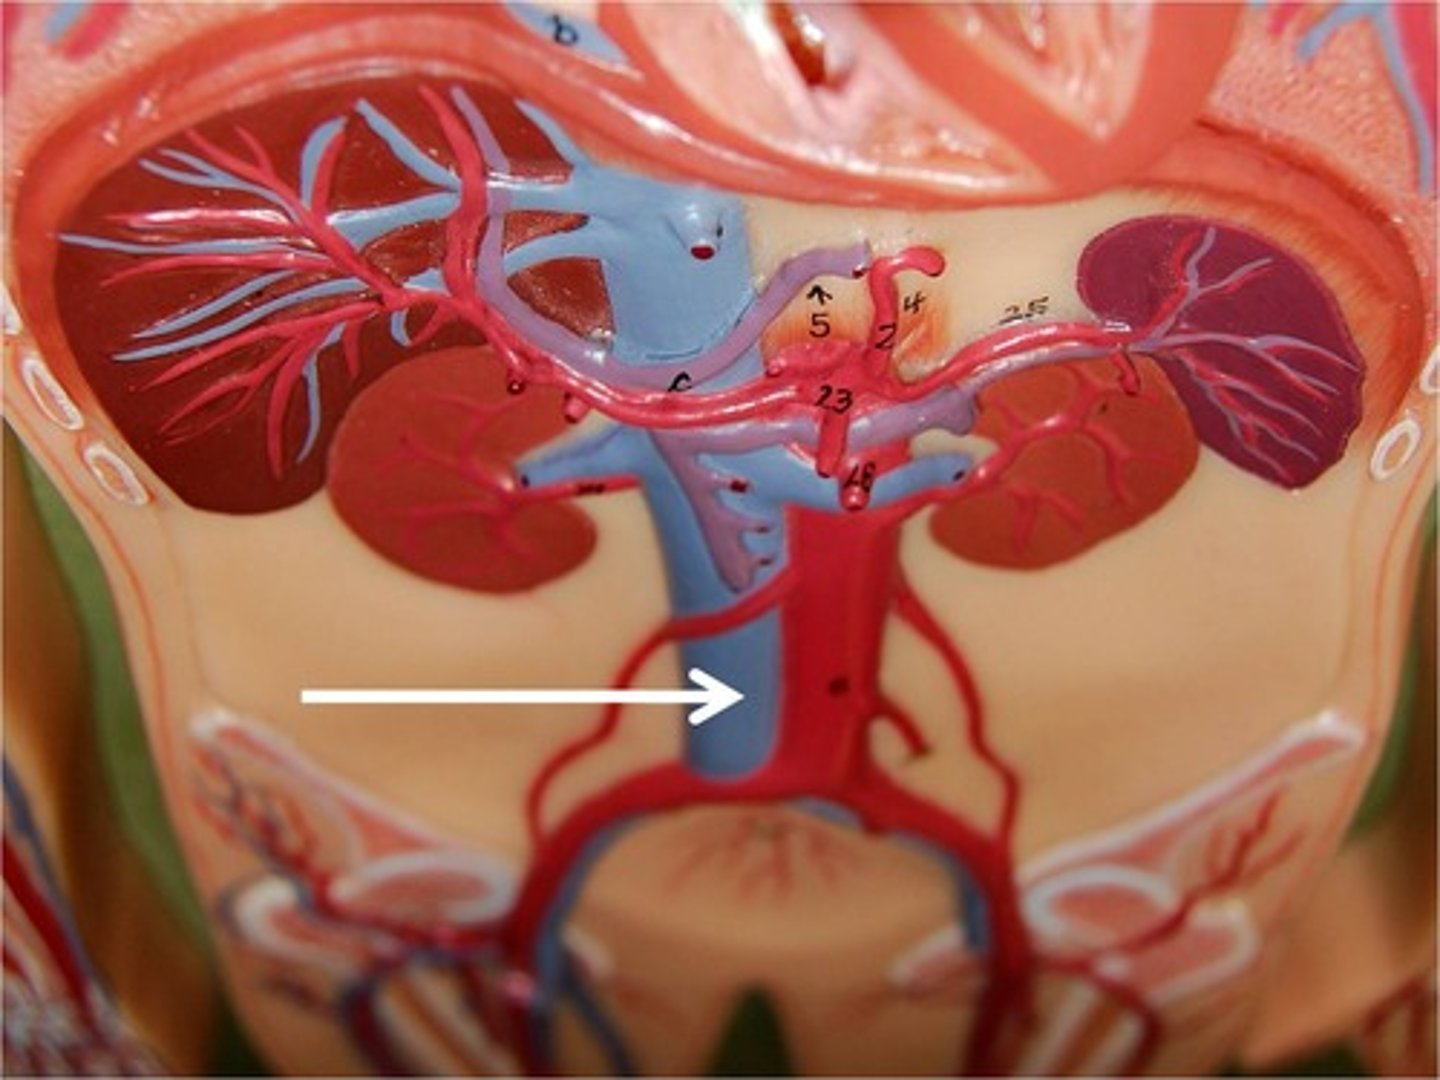

L4-L5

what level of vertebra is the inferior vena cava located

inferior vena cava